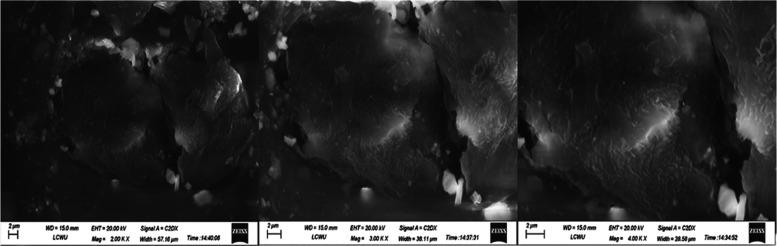

Ticagrelor (TCG) is a BCS class IV antiplatelet drug used to prevent platelet aggregation in patients with acute coronary syndrome, having poor solubility and permeability. The goal of this study was to develop a self-nanoemulsifying drug delivery system (SNEDDS) of TCG to improve its solubility and permeability. The excipients were selected based on the maximum solubility of TCG and observed by UV spectrophotometer. Different combinations of oil, surfactant, and co-surfactant (1:1, 2:1, and 3:1) were used to prepare TCG-SNEDDS formulations, and pseudo-ternary phase diagrams were plotted. The nanoemulsion region was observed. Clove oil (10-20%), Tween-80 (45-70%), and PEG-400 (20-45%) were used as an oil, surfactant, and co-surfactant, respectively. The selected formulations (F1, F2, F3, F4, F5, and F6) were analyzed for ζ potential, polydispersity index (PDI), ζ size, self-emulsification test, cloud point determination, thermodynamic studies, entrapment efficiency, Fourier transform infrared (FTIR) spectroscopy, X-ray diffraction (XRD), differential scanning calorimetry (DSC), thermogravimetric analysis (TGA), scanning electron microscopy (SEM), dissolution, permeation, and pharmacodynamic study. The TCG-SNEDDS formulations exhibited ζ potential from -9.92 to -6.23 mV, a ζ average of 11.85-260.4 nm, and good PDI. The drug release in phosphate buffer pH 6.8 from selected TCG-SNEDDS F4 was about 98.45%, and F6 was about 97.86%, displaying improved dissolution of TCG in 0.1 N HCl and phosphate buffer pH 6.8, in comparison to 28.05% of pure TCG suspension after 12 h. While the drug release in 0.1 N HCl from F4 was about 62.03%, F6 was about 73.57%, which is higher than 10.35% of the pure TCG suspension. In permeability studies, F4 also exhibited an improved apparent permeability of 2.7 × 10 0.6708 × 10 cm/s of pure drug suspension. The pharmacodynamic study in rabbits demonstrated enhanced antiplatelet activity from TCG-SNEDDS F4 compared to that from pure TCG suspension. These outcomes imply that the TCG-SNEDDS may serve as an effective means of enhancing TCG's antiplatelet activity by improving the solubility and permeability of TCG.

替格瑞洛(TCG)是一种生物药剂学分类系统(BCS)IV类抗血小板药物,用于预防急性冠脉综合征患者的血小板聚集,其溶解性和渗透性较差。本研究的目的是开发一种替格瑞洛的自纳米乳化药物递送系统(SNEDDS),以提高其溶解性和渗透性。根据替格瑞洛的最大溶解度选择辅料,并通过紫外分光光度计进行观察。使用油、表面活性剂和助表面活性剂的不同组合(1:1、2:1和3:1)制备替格瑞洛-SNEDDS制剂,并绘制伪三元相图。观察纳米乳区域。分别使用丁香油(10 - 20%)、吐温80(45 - 70%)和聚乙二醇400(20 - 45%)作为油、表面活性剂和助表面活性剂。对所选制剂(F1、F2、F3、F4、F5和F6)进行ζ电位、多分散指数(PDI)、ζ粒径、自乳化试验、浊点测定、热力学研究、包封率、傅里叶变换红外光谱(FTIR)、X射线衍射(XRD)、差示扫描量热法(DSC)、热重分析(TGA)、扫描电子显微镜(SEM)、溶出度、渗透率和药效学研究。替格瑞洛-SNEDDS制剂的ζ电位为-9.92至-6.23 mV,ζ平均粒径为11.85 - 260.4 nm,且具有良好的PDI。所选替格瑞洛-SNEDDS F4在pH 6.8磷酸盐缓冲液中的药物释放率约为98.45%,F6约为97.86%,与12小时后纯替格瑞洛混悬液的28.05%相比,替格瑞洛在0.1 N盐酸和pH 6.8磷酸盐缓冲液中的溶出度有所提高。而F4在0.1 N盐酸中的药物释放率约为62.03%,F6约为73.57%,高于纯替格瑞洛混悬液的10.35%。在渗透率研究中,F4的表观渗透率也有所提高,为2.7×10⁻⁶ cm/s,而纯药物混悬液为0.6708×10⁻⁶ cm/s。家兔体内的药效学研究表明,与纯替格瑞洛混悬液相比,替格瑞洛-SNEDDS F4的抗血小板活性增强。这些结果表明,替格瑞洛-SNEDDS可能是通过提高替格瑞洛的溶解性和渗透性来增强其抗血小板活性的有效手段。